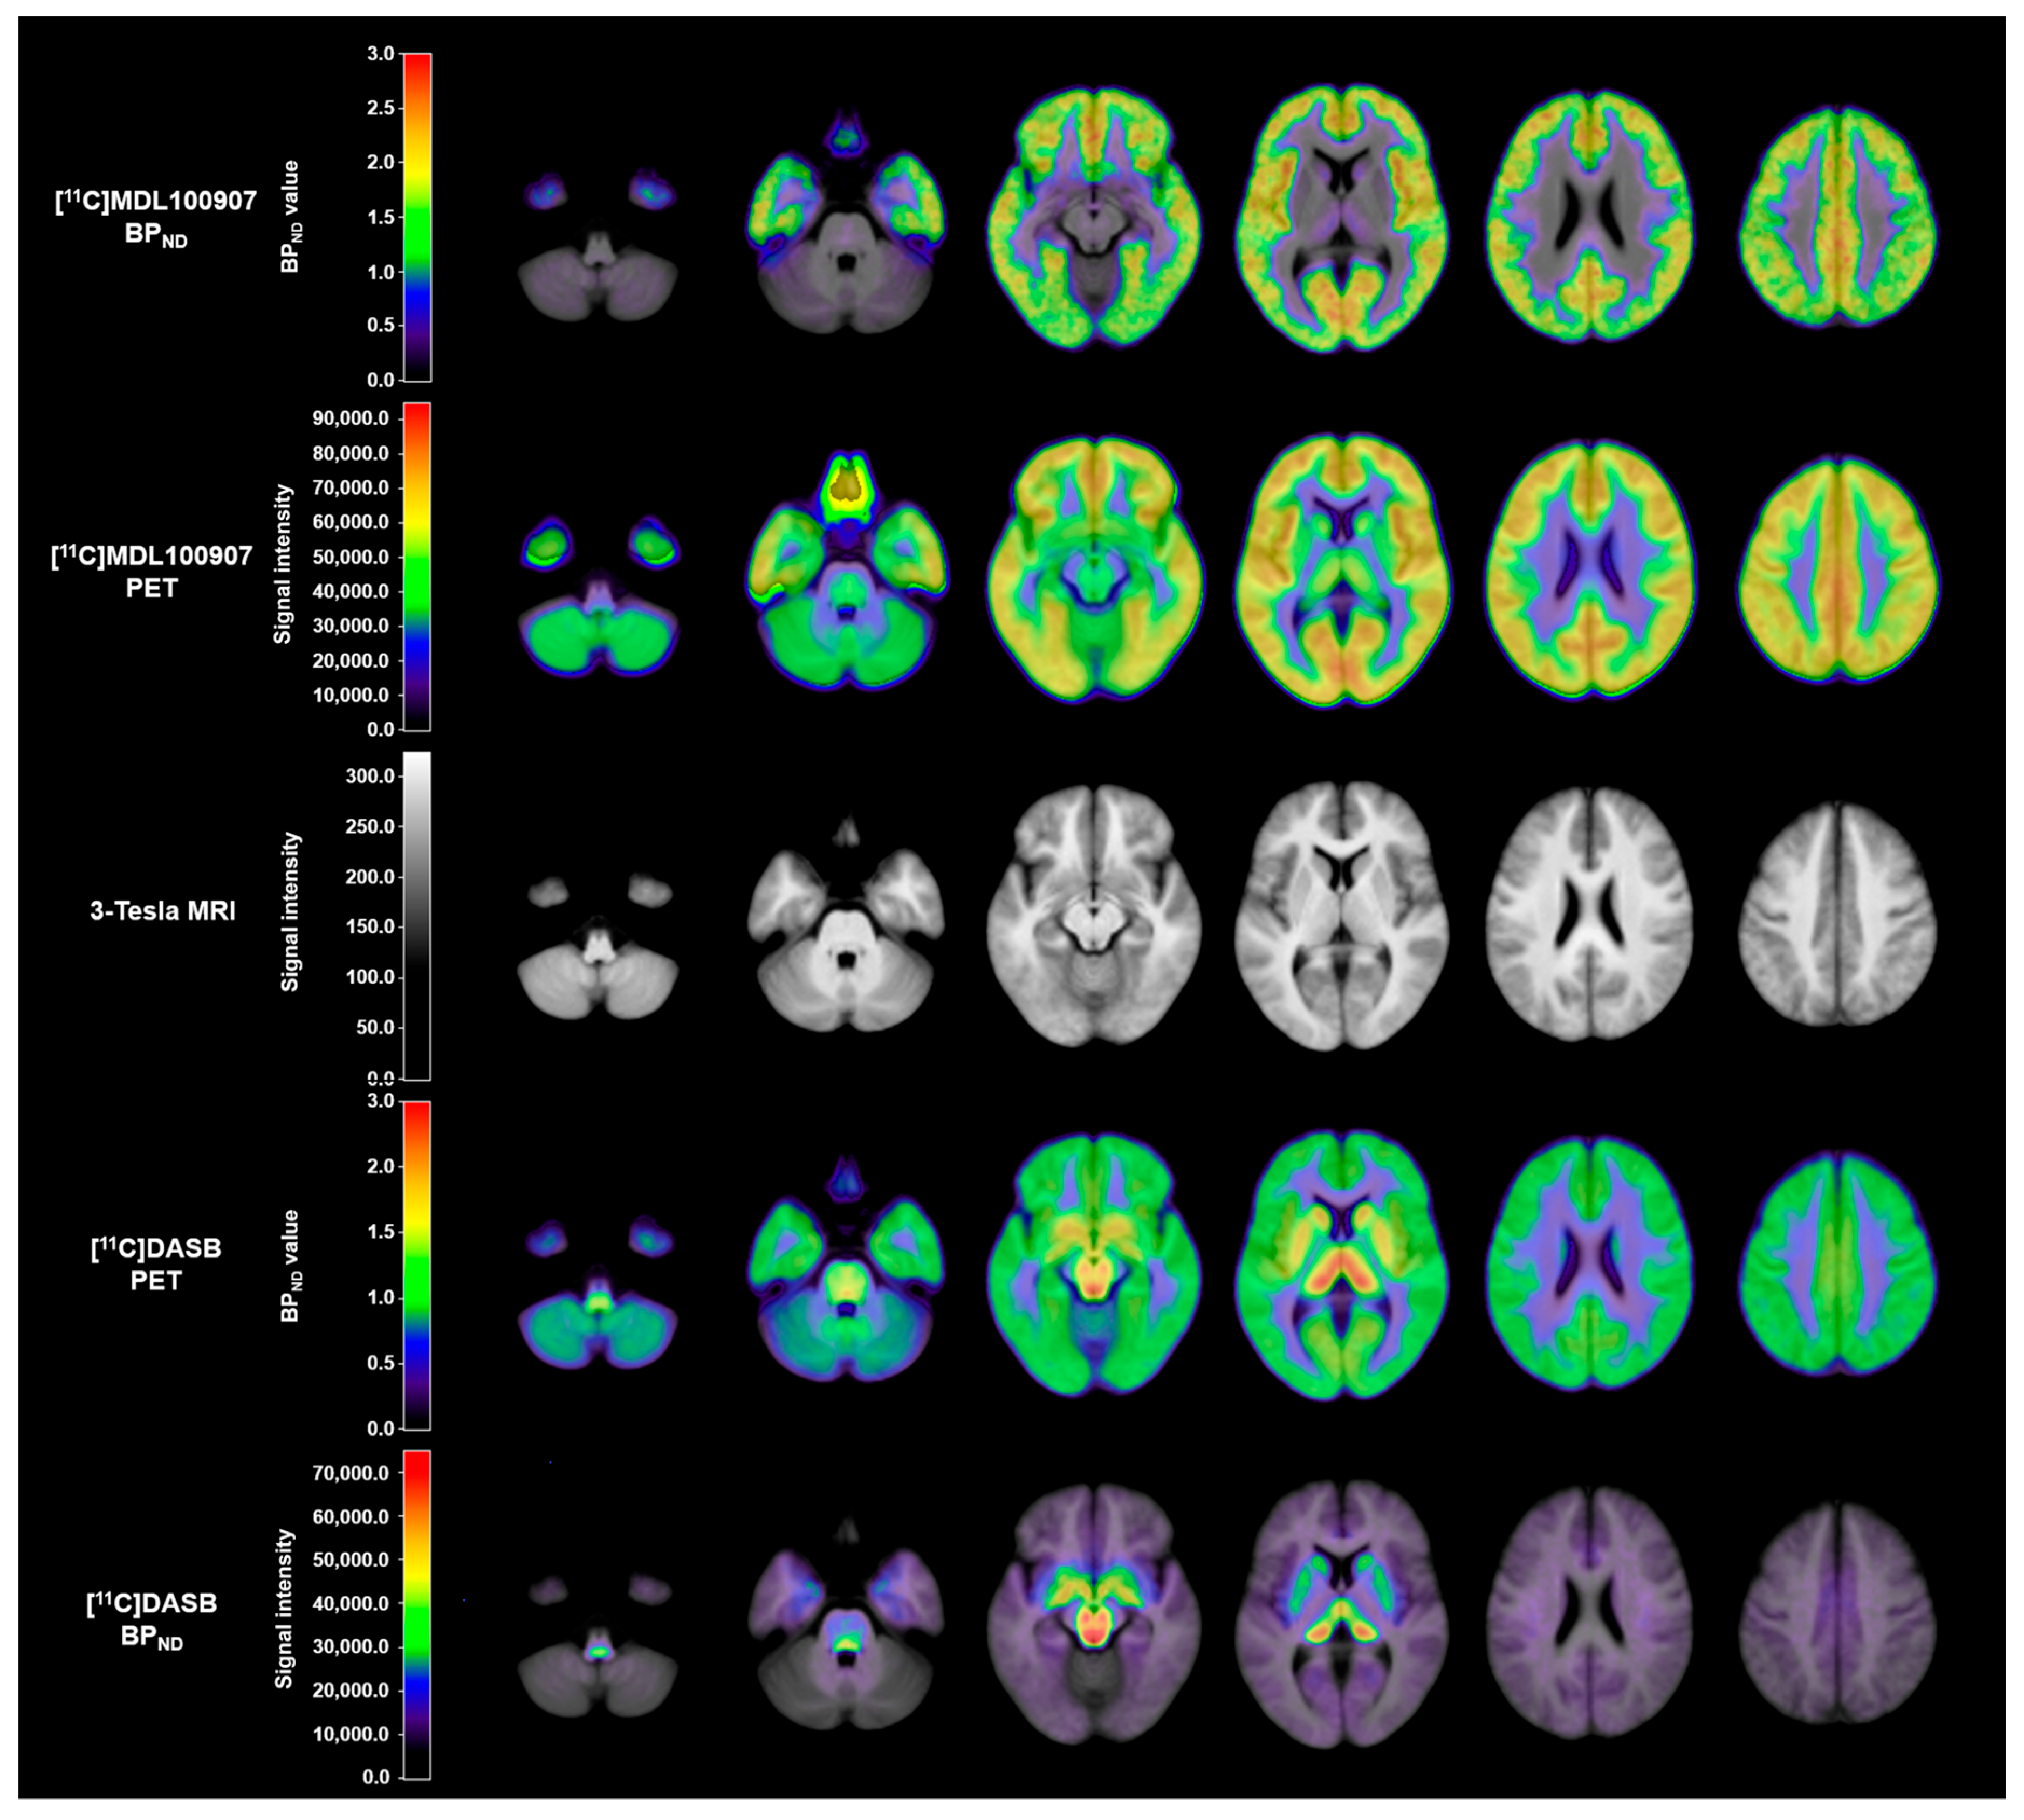

3. Discussion